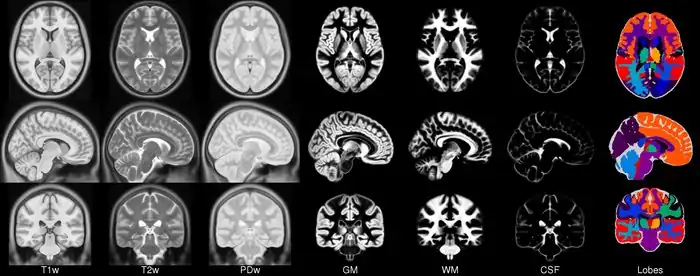

In 2001, within the context of the ICBM project (19) a concerted effort was undertaken by three sites (MNI, UCLA, RIC) to collect a set of full- brain volumetric images from a normative population specifically for the purposes of generating a model. 152 new subjects were scanned using T1, T2 and PD sequences as the MNI’s part of the ICBM project using a specific protocol (27). These images were acquired at a higher resolution than the original average 305 data and exhibit improved contrast due predominately to advances in imaging technology. Each individual was linearly registered to the average 305 and a new model was formed. In total, three models were created at the MNI, the ICBM152_T1, ICBM152_T2 and ICBM152_PD from 152 normal subjects. This resulting model is now known as the ICBM152 (although the model itself has not been published). One advantage of this model is that it exhibits better contrast and better definition of the top of the brain and the bottom of the cerebellum due to the increased coverage during acquisition.

The entirely automatic analysis pipeline of this data also included grey/white matter segmentation via spatial priors (41). The averaged results of these segmentations formed the first MNI parametric maps of grey and white matter. The maps were never made publicly available in isolation but have formed parts of other packages for some time including SPM, FSL AIR and as models of grey matter for EEG source location in VARETTA and BRAINWAVE.

The native data from these acquisitions was 256x256 with 1mm slices. The final image resolution of this data was 181x217x181 with 1mm isotropic voxels.